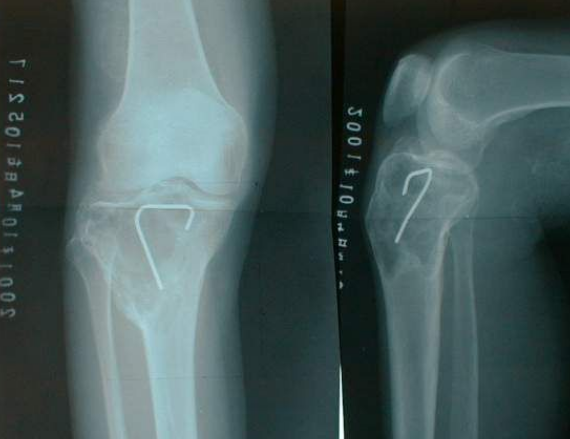

骨巨细胞瘤(GCTB)是一种罕见的侵略性良性溶骨性肿瘤,其中的骨破坏是由一种称为RANK配体的蛋白质介导的。这种蛋白质调节破骨细胞(破坏骨骼的细胞)的活性。GCTB通常会影响20至40岁之间的年轻人。从历史上看,GCTB患者的唯一治疗选择是手术。但是,接受手术的患者经常会复发疾病或造成毁灭性后果,例如截肢。而且,大约25%至30%的GCTB患者必须接受关节置换术。

地诺单抗是一种靶向药物,称为单克隆抗体。该药物靶向RANK配体,从而抑制骨破坏并可能消除巨细胞。地诺单抗于2010年获得批准,可用于预防骨并发症,例如因实体(非血液相关)癌症而发生骨转移的患者的骨折-现在适用于无法通过手术切除GCTB的患者或可能导致严重发病的外科手术例如肢体脱落或关节切除。